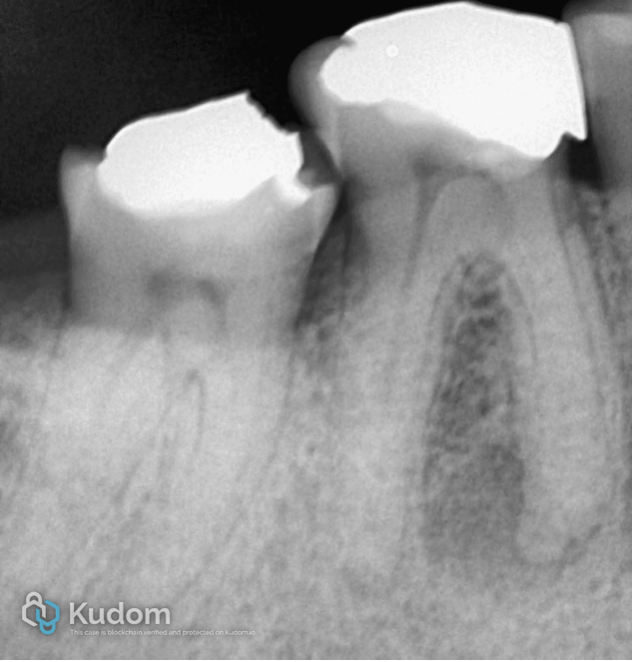

Fig. 7

One-and-a-half–year clinical follow-up demonstrating stable restorations with satisfactory marginal adaptation, preserved occlusal anatomy, and healthy surrounding soft tissues, indicating favorable long-term clinical performance.

Fig. 8

One-and-a-half–year radiographic follow-up demonstrating maintained obturation integrity, healing of periapical lesion, and absence of pathological changes, indicating favorable long-term endodontic outcome